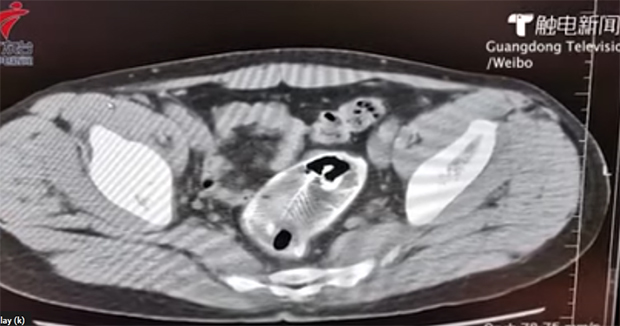

Pacijent se javio u bolnicu u kineskoj provinciji Guangdong početkom juna nakon što je osetio jaku bol u stomaku.

Doktori su ga poslali na pretrage koje su otkrile uzrok problema – slatkovodnu ribu. Šokirane medicinske sestre upitale su 30-godišnjaka što mu riba radi u anusu, da bi im on odgovorio da je slučajno seo na nju.

Riba je bila prevelika da se ukloni endoskopijom pa su je morali hiruški ukloniti. Tako su otkrili da su bodljikave peraje probile zid debelog creva radoznalog Kineza.